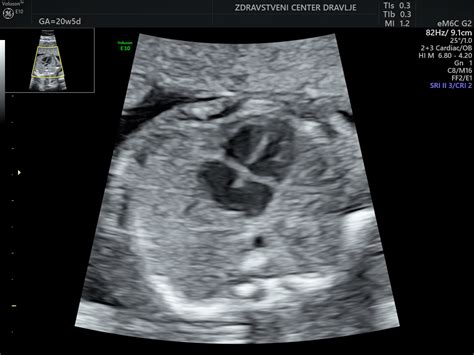

Med 19. in 20. tednom se možgani intenzivno razvijajo, plod pa nadaljuje z intenzivno rastjo. V 20. tednu plod meri približno 25 cm v dolžino in tehta okoli 300 g. Na koži se pojavi verniks, bela mastna zaščitna snov, ki ščiti kožo pred dolgotrajno izpostavljenostjo plodovnici. V tem času se običajno opravi morfološki ultrazvočni pregled ploda, s katerim se oceni njegov razvoj in določi lega posteljice. Nosečnice, še posebej tiste, ki pričakujejo prvega otroka, bodo morda v tem obdobju prvič občutile gibe ploda.